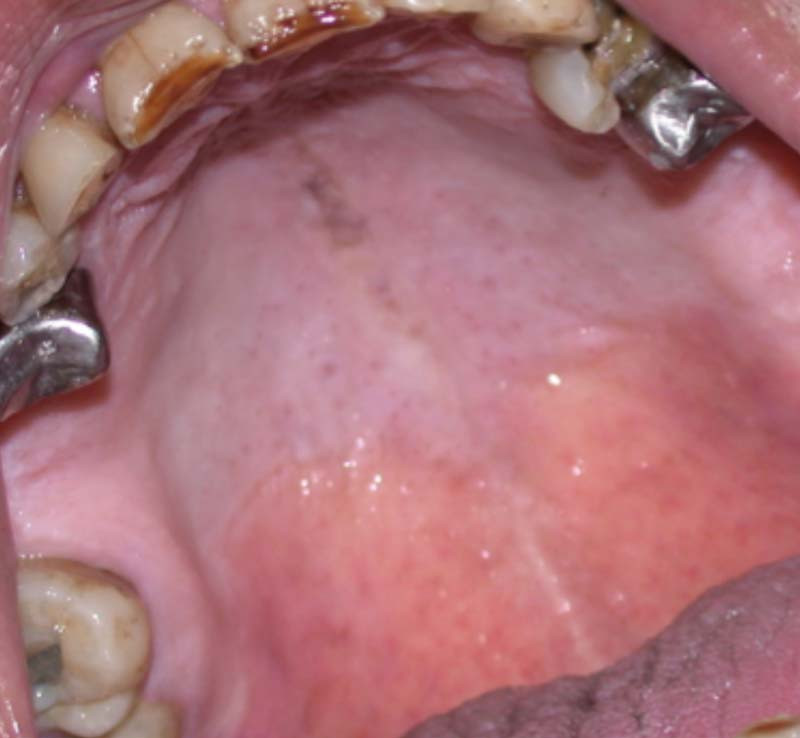

Femme de 46 ans qui a consulté pour une douleur palatine médiane présente depuis quatre mois.

Depuis quatre mois, la patiente se plaint d’une douleur palatine localisée, continue.